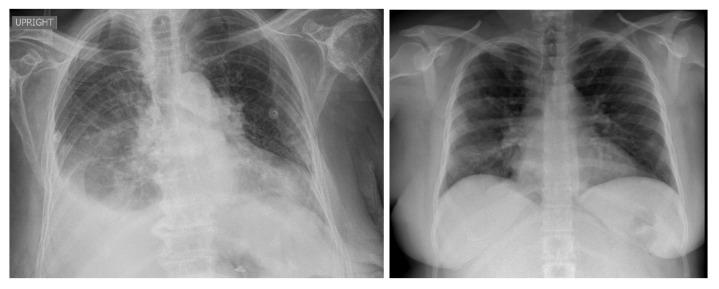

COVID-19,which is caused by the severe acute respiratory syndrome coronavirus 2 (SARS-CoV-2), is one of the worst pandemics in recent history. The identification of patients suspected to be infected with COVID-19 is becoming crucial to reduce its spread. We aimed to validate and test a deep learning model to detect COVID-19 based on chest X-rays. The recent deep convolutional neural network (CNN) RegNetX032 was adapted for detecting COVID-19 from chest X-ray (CXR) images using polymerase chain reaction (RT-PCR) as a reference. The model was customized and trained on five datasets containing more than 15,000 CXR images (including 4148COVID-19-positive cases) and then tested on 321 images (150 COVID-19-positive) from Montfort Hospital. Twenty percent of the data from the five datasets were used as validation data for hyperparameter optimization. Each CXR image was processed by the model to detect COVID-19. Multi-binary classifications were proposed, such as: COVID-19 vs. normal, COVID-19 + pneumonia vs. normal, and pneumonia vs. normal. The performance results were based on the area under the curve (AUC), sensitivity, and specificity. In addition, an explainability model was developed that demonstrated the high performance and high generalization degree of the proposed model in detecting and highlighting the signs of the disease. The fine-tuned RegNetX032 model achieved an overall accuracy score of 96.0%, with an AUC score of 99.1%. The model showed a superior sensitivity of 98.0% in detecting signs from CXR images of COVID-19 patients, and a specificity of 93.0% in detecting healthy CXR images. A second scenario compared COVID-19 + pneumonia vs. normal (healthy X-ray) patients. The model achieved an overall score of 99.1% (AUC) with a sensitivity of 96.0% and specificity of 93.0% on the Montfort dataset. For the validation set, the model achieved an average accuracy of 98.6%, an AUC score of 98.0%, a sensitivity of 98.0%, and a specificity of 96.0% for detection (COVID-19 patients vs. healthy patients). The second scenario compared COVID-19 + pneumonia vs. normal patients. The model achieved an overall score of 98.8% (AUC) with a sensitivity of 97.0% and a specificity of 96.0%. This robust deep learning model demonstrated excellent performance in detecting COVID-19 from chest X-rays. This model could be used to automate the detection of COVID-19 and improve decision making for patient triage and isolation in hospital settings. This could also be used as a complementary aid for radiologists or clinicians when differentiating to make smart decisions.

COVID-19 是由严重急性呼吸综合征冠状病毒 2(SARS-CoV-2)引起的,是最近历史上最严重的大流行之一。识别疑似感染 COVID-19 的患者对于减少其传播至关重要。我们旨在验证和测试一种基于胸部 X 光片检测 COVID-19 的深度学习模型。最近的深度卷积神经网络(CNN)RegNetX032 经过适应,可使用聚合酶链反应(RT-PCR)作为参考,从胸部 X 光(CXR)图像中检测 COVID-19。该模型在包含超过 15000 张 CXR 图像(包括 4148 例 COVID-19 阳性病例)的五个数据集上进行了定制和训练,然后在蒙福特医院的 321 张图像(150 例 COVID-19 阳性病例)上进行了测试。五个数据集的 20%的数据用于超参数优化的验证数据。模型处理每张 CXR 图像以检测 COVID-19。提出了多二进制分类,例如:COVID-19 与正常,COVID-19+肺炎与正常,肺炎与正常。性能结果基于曲线下面积(AUC)、敏感性和特异性。此外,还开发了一个可解释性模型,该模型证明了所提出的模型在检测和突出疾病迹象方面具有出色的性能和高度的泛化能力。经过微调的 RegNetX032 模型的整体准确率达到 96.0%,AUC 评分为 99.1%。该模型在检测 COVID-19 患者的 CXR 图像中的迹象方面表现出优越的敏感性,达到 98.0%,在检测健康 CXR 图像方面具有 93.0%的特异性。第二个场景比较了 COVID-19+肺炎与正常(健康 X 射线)患者。该模型在蒙福特数据集上的总体评分为 99.1%(AUC),具有 96.0%的敏感性和 93.0%的特异性。对于验证集,该模型的平均准确率为 98.6%,AUC 评分为 98.0%,敏感性为 98.0%,特异性为 96.0%用于检测(COVID-19 患者与健康患者)。第二个场景比较了 COVID-19+肺炎与正常患者。该模型的总体评分为 98.8%(AUC),敏感性为 97.0%,特异性为 96.0%。该强大的深度学习模型在从胸部 X 光片中检测 COVID-19 方面表现出出色的性能。该模型可用于自动检测 COVID-19,并提高医院环境中患者分诊和隔离的决策能力。当进行区分以做出明智决策时,它也可以作为放射科医生或临床医生的辅助工具。